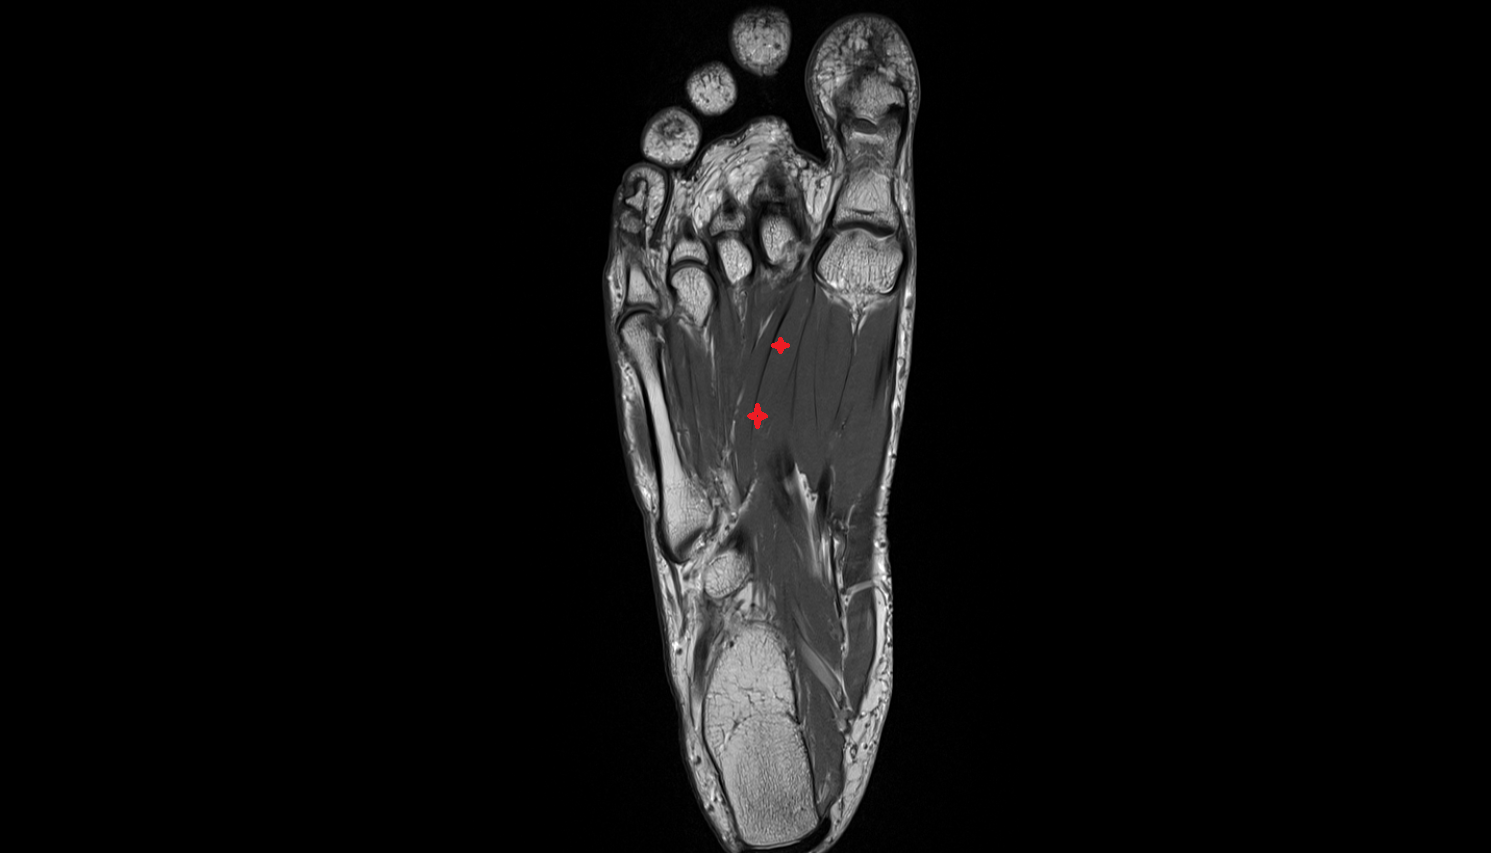

- Plantar aponeurosis